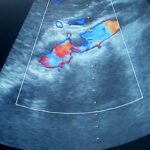

Color Doppler abdomena je ultrazvučna tehnika pregleda kojom se pregledavaju krvne žile unutar trbušne šupljine te se procjenjuje prokrvljenost unutrašnjih organa. Sama tehnika color ili obojenog Dopplera zasnovana je na fizikalnom zakonu poznatom pod imenom Dopplerov efekt a koji nam opisuje odnose između objekta koji se kreće i ultrazvučnih valova koji ga prate u tom kretanju. Na osnovu tih parametara možemo računati volumene i brzine protoka krvi kroz ispitivane krvne žile i organe. Ispitivanje renalnih arterija sastavni je dio dijagnostičke obrade svih pacijenata koji imaju povišen arterijski tlak. Procjena ateroskleroze, odnosno suženja arterija, kao i praćenje dinamike razvoja bolesti, te okrivanje abdominalne aneurizme (proširenja krvne žile) kao izrazito opasnog stanja moguće je pomoću color Dopplera.

Procjena venske cirkulacije odnosno povrata krvi ka srcu putem vena moguća je također ovom tehnikom. Nadalje se color Dopplerom dobivaju iznimno važne informacije o prokrvljenosti tumora i drugih patoloških procesa, kao što je ciroza jetara, unutar trbušne šupljine. Evaluacija i kontinuirano praćenje prokrvljenosti transplantiranih organa (bubrega, jetara itd.) vrlo elegantno se radi uz pomoć color Dopplera. Kao i kod ultrazvučnog pregleda abdomena rezultati jako ovise o kvaliteti ultrazvučnog aparata pomoću kojeg se radi color Doppler abdomena, kao i o iskustvu i umijeću liječnika koji vrši pregled.